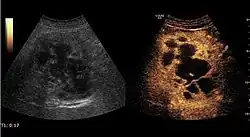

US examination is required to detect liver metastases in patients with oncologic history. In addition, the method can incidentally detect metastases in asymptomatic patients. Early identification (small sizes, small number) is important to establish an optimal course of treatment which can be complex (chemotherapy, radiofrequency ablation, surgical resection) but welcomed. In addition, discrimination of synchronous lesions that have a different nature is also important knowing that up to 25–50% of liver lesions less than 2 cm detected in cancer patients may be benign . US sensitivity for metastases detection varies depending on the examiner's experience and the equipment used and ranges between 40 and 80% . Sensitivity is conditioned by the size and acoustic impedance of the nodules. For a lesion diameter below 10 mm US accuracy is greatly reduced, reaching approx. 20%. Other elements contributing to lower US performance are: excessive obesity, fatty liver disease, hypomobility of the diaphragm, and certain patterns of hyperechoic or isoechoic metastases that can be overlooked or can mimic benign conditions. Conventional US appearance of metastases is uncharacteristic, consisting of circumscribed lesions, with clear, imprecise or "halo" delineation, with homogeneous or heterogeneous echo pattern. They can be single (often liver metastases from colonic neoplasm) or multiple. Echogenity is variable. When increased, they can compress the bile ducts (which may be dilated) and the liver vessels. Liver involvement can be segmental, lobar or generalized. In this situation a pronounced hepatomegaly occurs. Generally, metastases have non-characteristic Doppler vascular pattern, with few exceptions (carcinoid metastases). Cyst-adenocarcinoma metastases due to semifluid content may have a transonic appearance. When increasing, they can result in central necrosis. CEUS examination is a real breakthrough for detection and characterization of liver metastases.

Increased performance is based on identifying specific vascular patterns during the arterial phase and seeing metastases in contrast to normal liver parenchyma during the sinusoidal phase. CEUS increased accuracy is due to the different behavior of normal liver parenchyma (captures CA in Kuppfer cells) against tumor parenchyma (does not contain Kuppfer cells, therefore CEUS appearance is hypoechoic). To this adds the particularities of intratumoral circulation represented by a reduced arterial bed compared to that of the surrounding normal liver and the absence of the portal vessels . In terms of vascularity, metastases can be hypovascular (in gastric, colonic, pancreatic or ovarian adenocarcinomas) with hypoechoic pattern during arterial phase, and similar during portal venous and late phases, respectively hypervascular (neuroendocrine tumors, malignant melanoma, sarcomas, renal, breast or thyroid tumors) with hyperechoic appearance during arterial phase, with washout during the portal venous phase and hypoechoic pattern 30 seconds after injection.